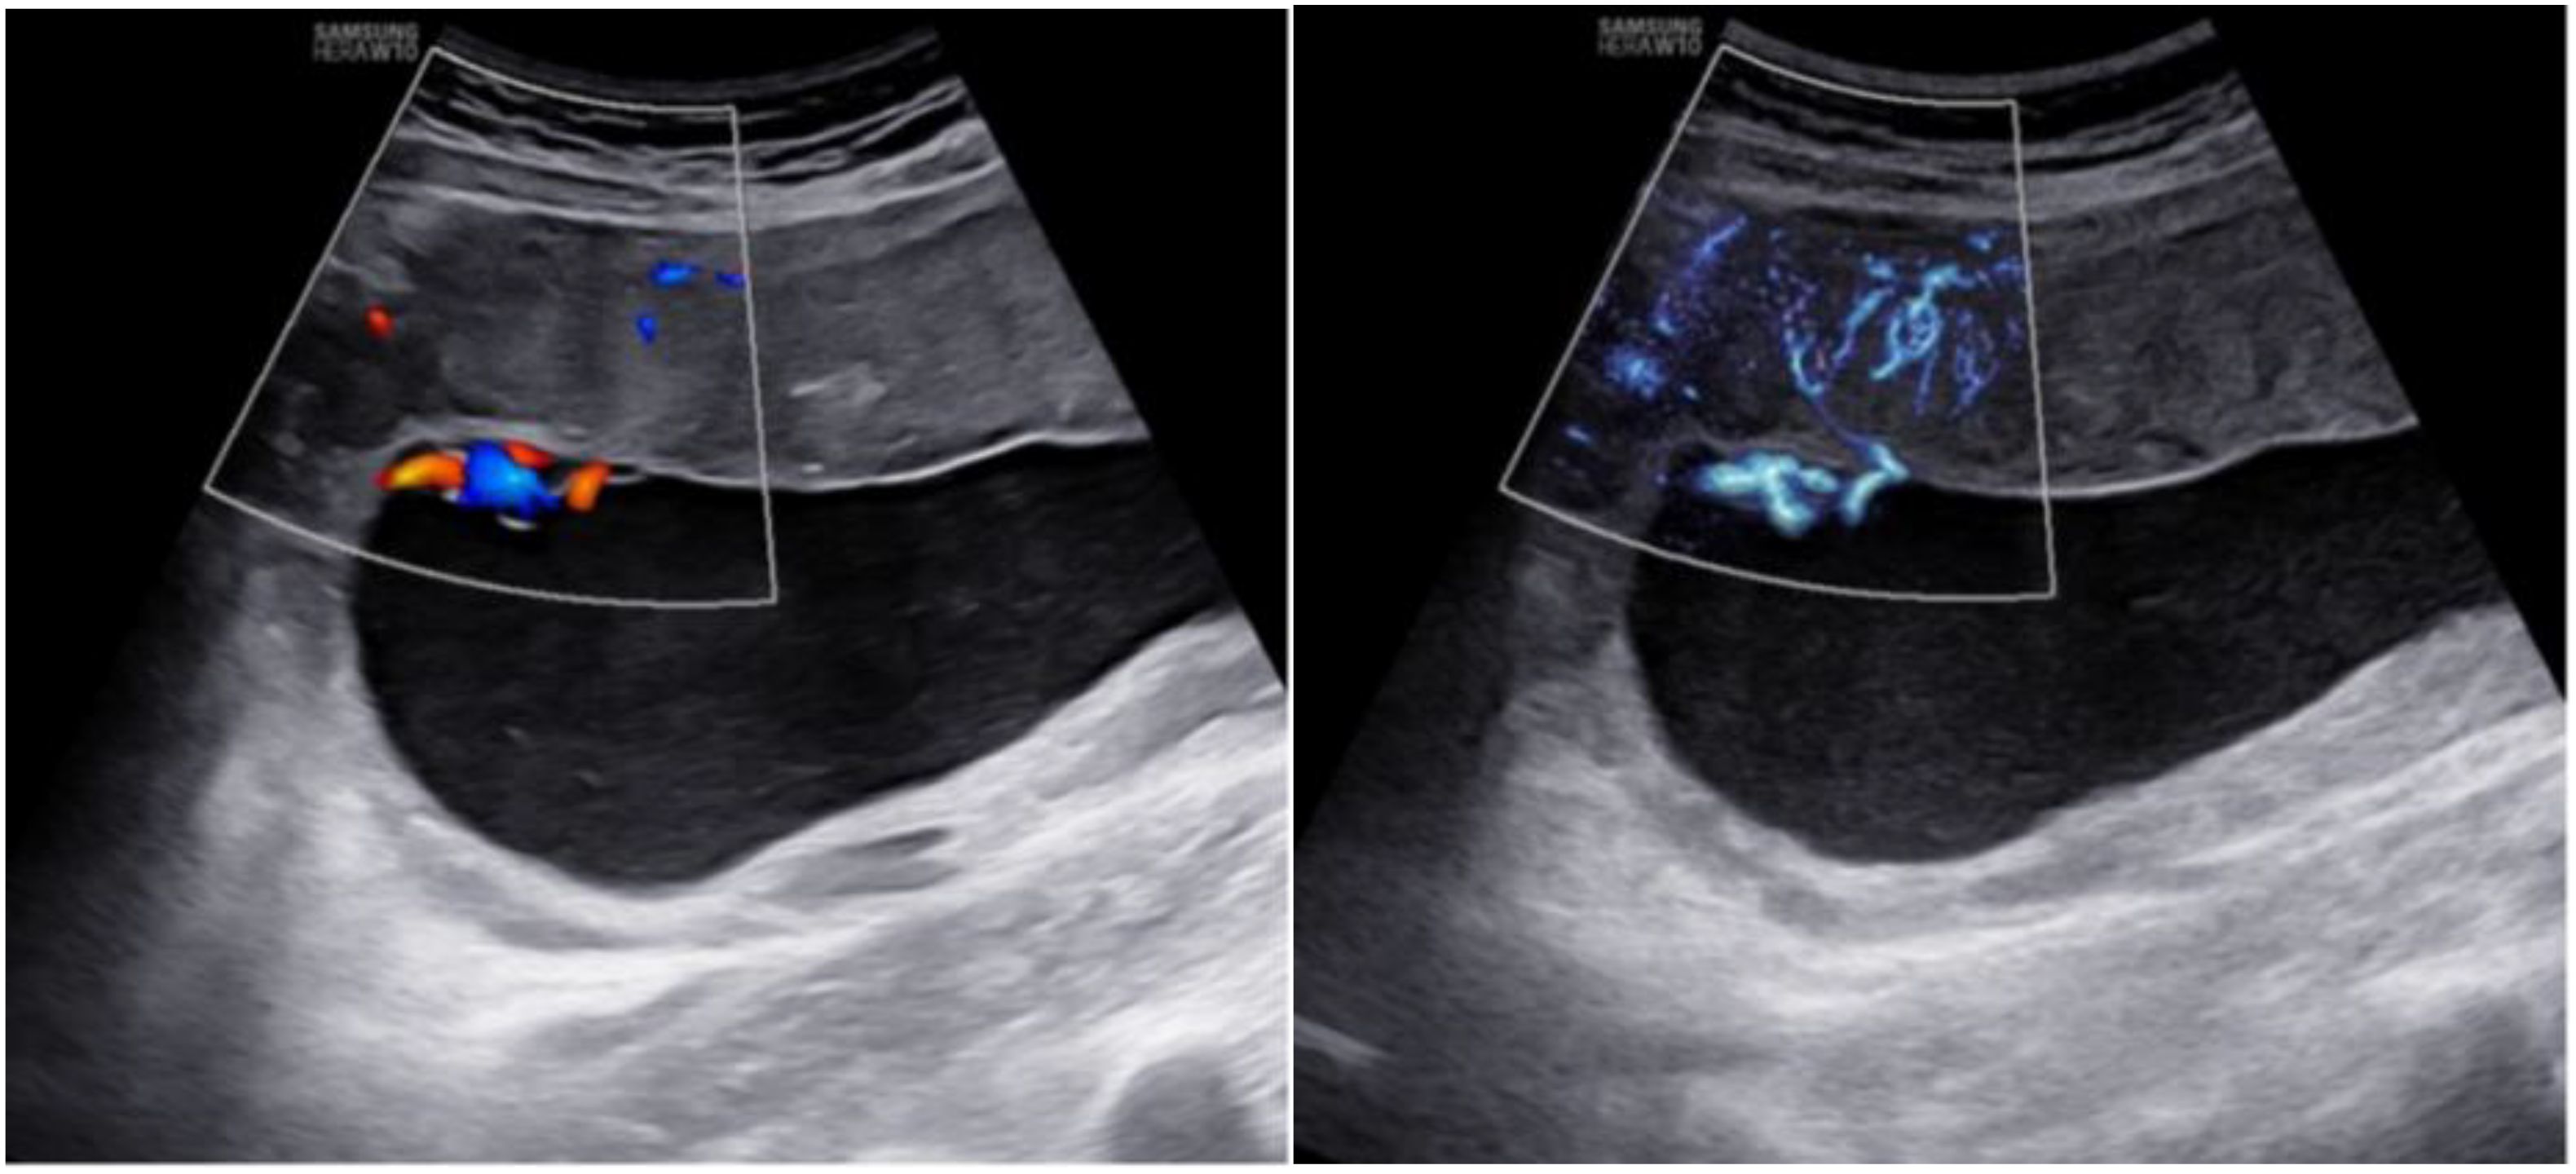

In addition, MV-Flow imaging was able to depict smaller, slow-flow vessels within the placenta, which were not visible using routine Doppler ultrasound (Figure 3). Figure 2 shows group comparisons between the control, the GDM1 group, and the GDM2 group regarding each of the three MV-Flow parameters obtained in the placenta. Participants in the GDM1 group had greater MVI values in the upper or lower parts of the placenta than participants in the control and GDM2 group (all P < 0.05). None of the MVI in the other parts of the placenta showed group differences. There was a moderate correlation between MVImean (%) and birthweight (g) in the GDM1 group (Pearson: r = 0.539; P < 0.001). However, there was no significant correlation between MVImean (%) and birthweight (g) in the GDM2 group (Pearson: r = −0.416; P = 0.109). In the secondary analyses within GDM1, higher MVImean (40.81% ± 7.83%) was significantly associated with higher neonate birthweight (3,135.41 ± 370.64 g) (adj.R2 = 0.28, F = 24.22, P < 0.001; t = 4.92, P < 0.001; standardized β = 0.539) (Figure 4). Pregnancy weight gain, pre-BMI, MVImean, and birthweight were included in the multivariable analysis. MVImean, pregnancy weight gain, and pre-BMI were positively associated with birthweight (standardized β = 0.532, P < 0.001; standardized β = 0.236, P = 0.027; standardized β = 0.307, P = 0.004, respectively). The receiver operating characteristic (ROC) curve analysis indicated that MVImean can well discriminate the normal and GDM pregnancies, with an area under the curve (AUC) value of 0.593 ([95% CI, 0.507–0.68]; P = 0.031; Figure 5). The sensitivity and specificity of MVImean for discriminating between normal and GDM pregnancies were 56.8% and 69.6%, respectively. After the GDM2 group was excluded from the GDM group, the results suggested that MVImean was able to separate well GDM pregnancies from normal pregnancies, with an AUC value of 0.639 ([95% CI, 0.547–0.731]; P = 0.003; Figure 5). The Youden index, indicating the optimal point along the ROC curve for GDM prediction, was calculated at the MVImean level of 38.95%, with a specificity of 69.6% and sensitivity of 62.9% at this level.

Ultrasound images showing blood flow in the placenta. The left image uses color Doppler to display red and blue areas indicating blood direction.The right image uses MV-Flow to highlight additional blood flow details in light blue.

Figure 3. Placental imaging by routine Doppler ultrasound (left) and MV-Flow (right).